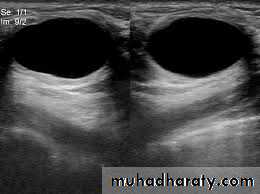

b-uls both for diagnosis and to guide biopsy

c-magnetic resonance useful in symptomatic patient with breast implant where US is not diagnostic and also used in to detect local recurrence where US and mammography are un helpful

3-biopsy usually US guided